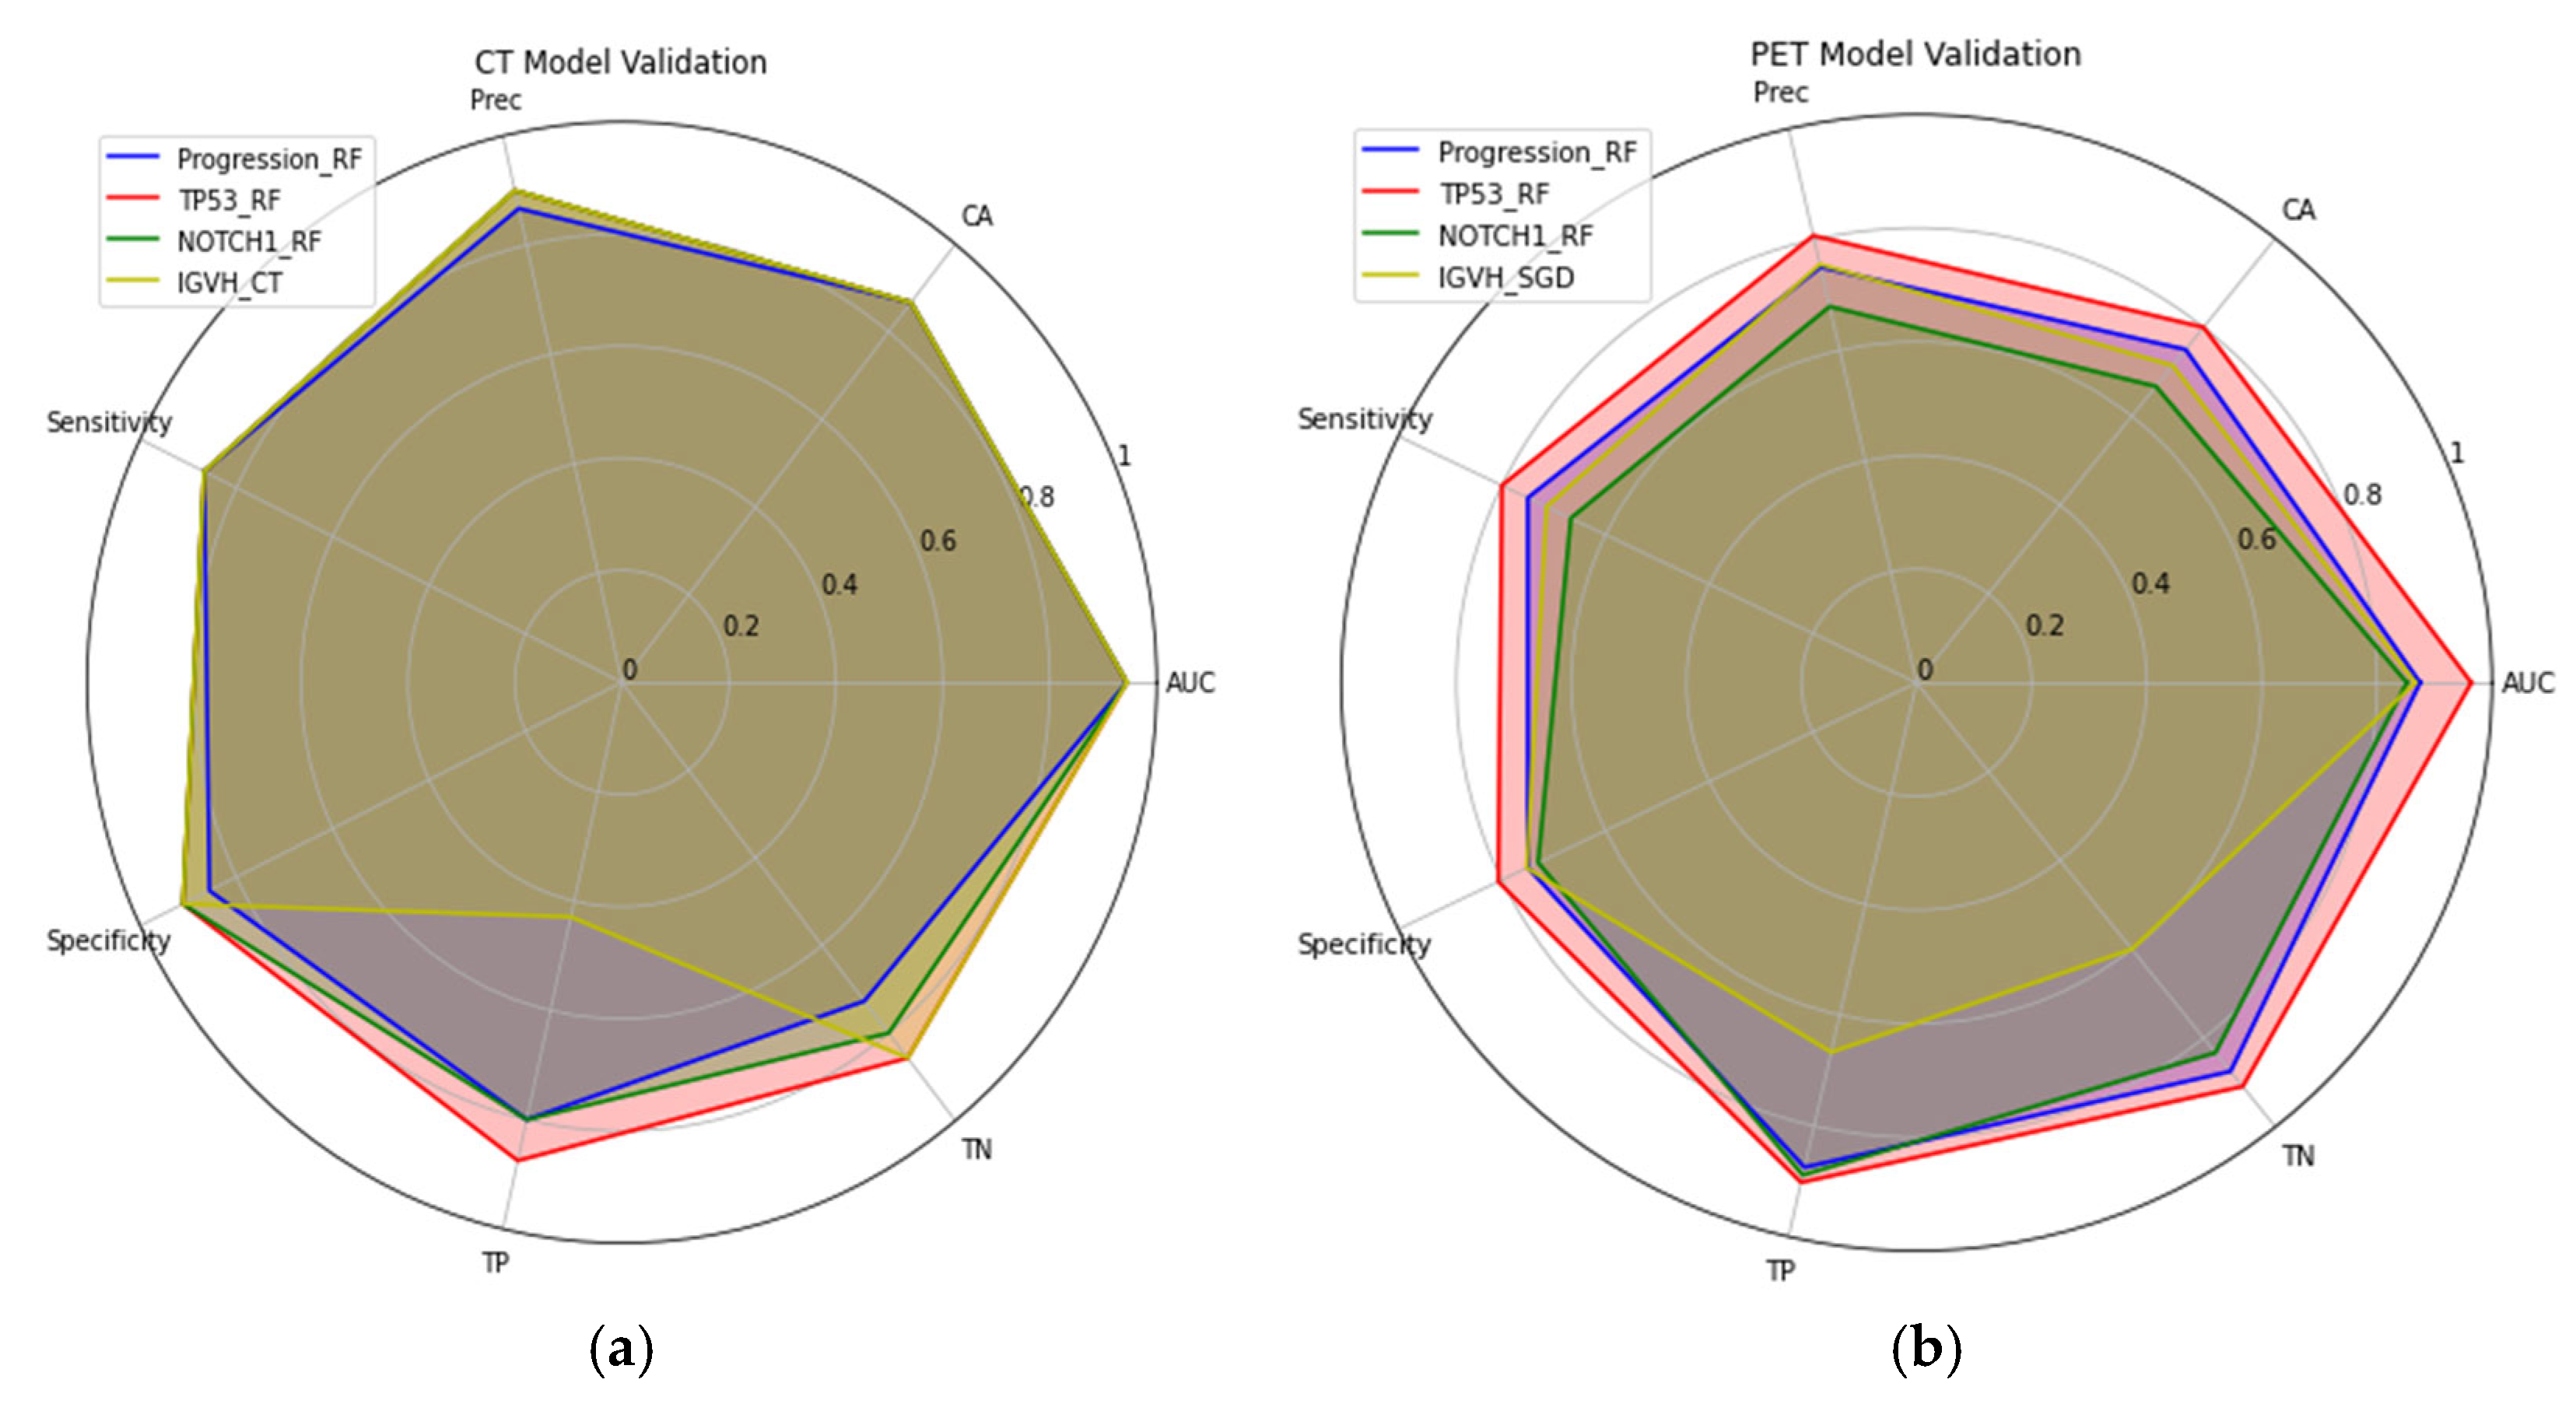

3.3. Machine Learning Models’ Performances

| CT Model | AUC | CA | Precision | Sensitivity | Specificity | TP | TN |

|---|---|---|---|---|---|---|---|

| Progression_RF | 0.94 | 0.87 | 0.87 | 0.87 | 0.86 | 0.80 | 0.73 |

| TP53_RF | 0.94 | 0.87 | 0.90 | 0.87 | 0.91 | 0.87 | 0.86 |

| NOTCH1_RF | 0.94 | 0.87 | 0.90 | 0.87 | 0.91 | 0.80 | 0.8 |

| IGVH_RF | 0.94 | 0.87 | 0.90 | 0.87 | 0.91 | 0.43 | 0.86 |

| PET Model | |||||||

| Progression_RF | 0.88 | 0.75 | 0.75 | 0.75 | 0.75 | 0.87 | 87.50 |

| TP53_RF | 0.96 | 0.80 | 0.81 | 0.80 | 0.81 | 0.90 | 0.91 |

| NOTCH1_RF | 0.85 | 0.67 | 0.68 | 0.67 | 0.73 | 0.89 | 0.83 |

| IGVH_SGD | 0.87 | 0.71 | 0.76 | 0.71 | 0.75 | 0.67 | 0.60 |